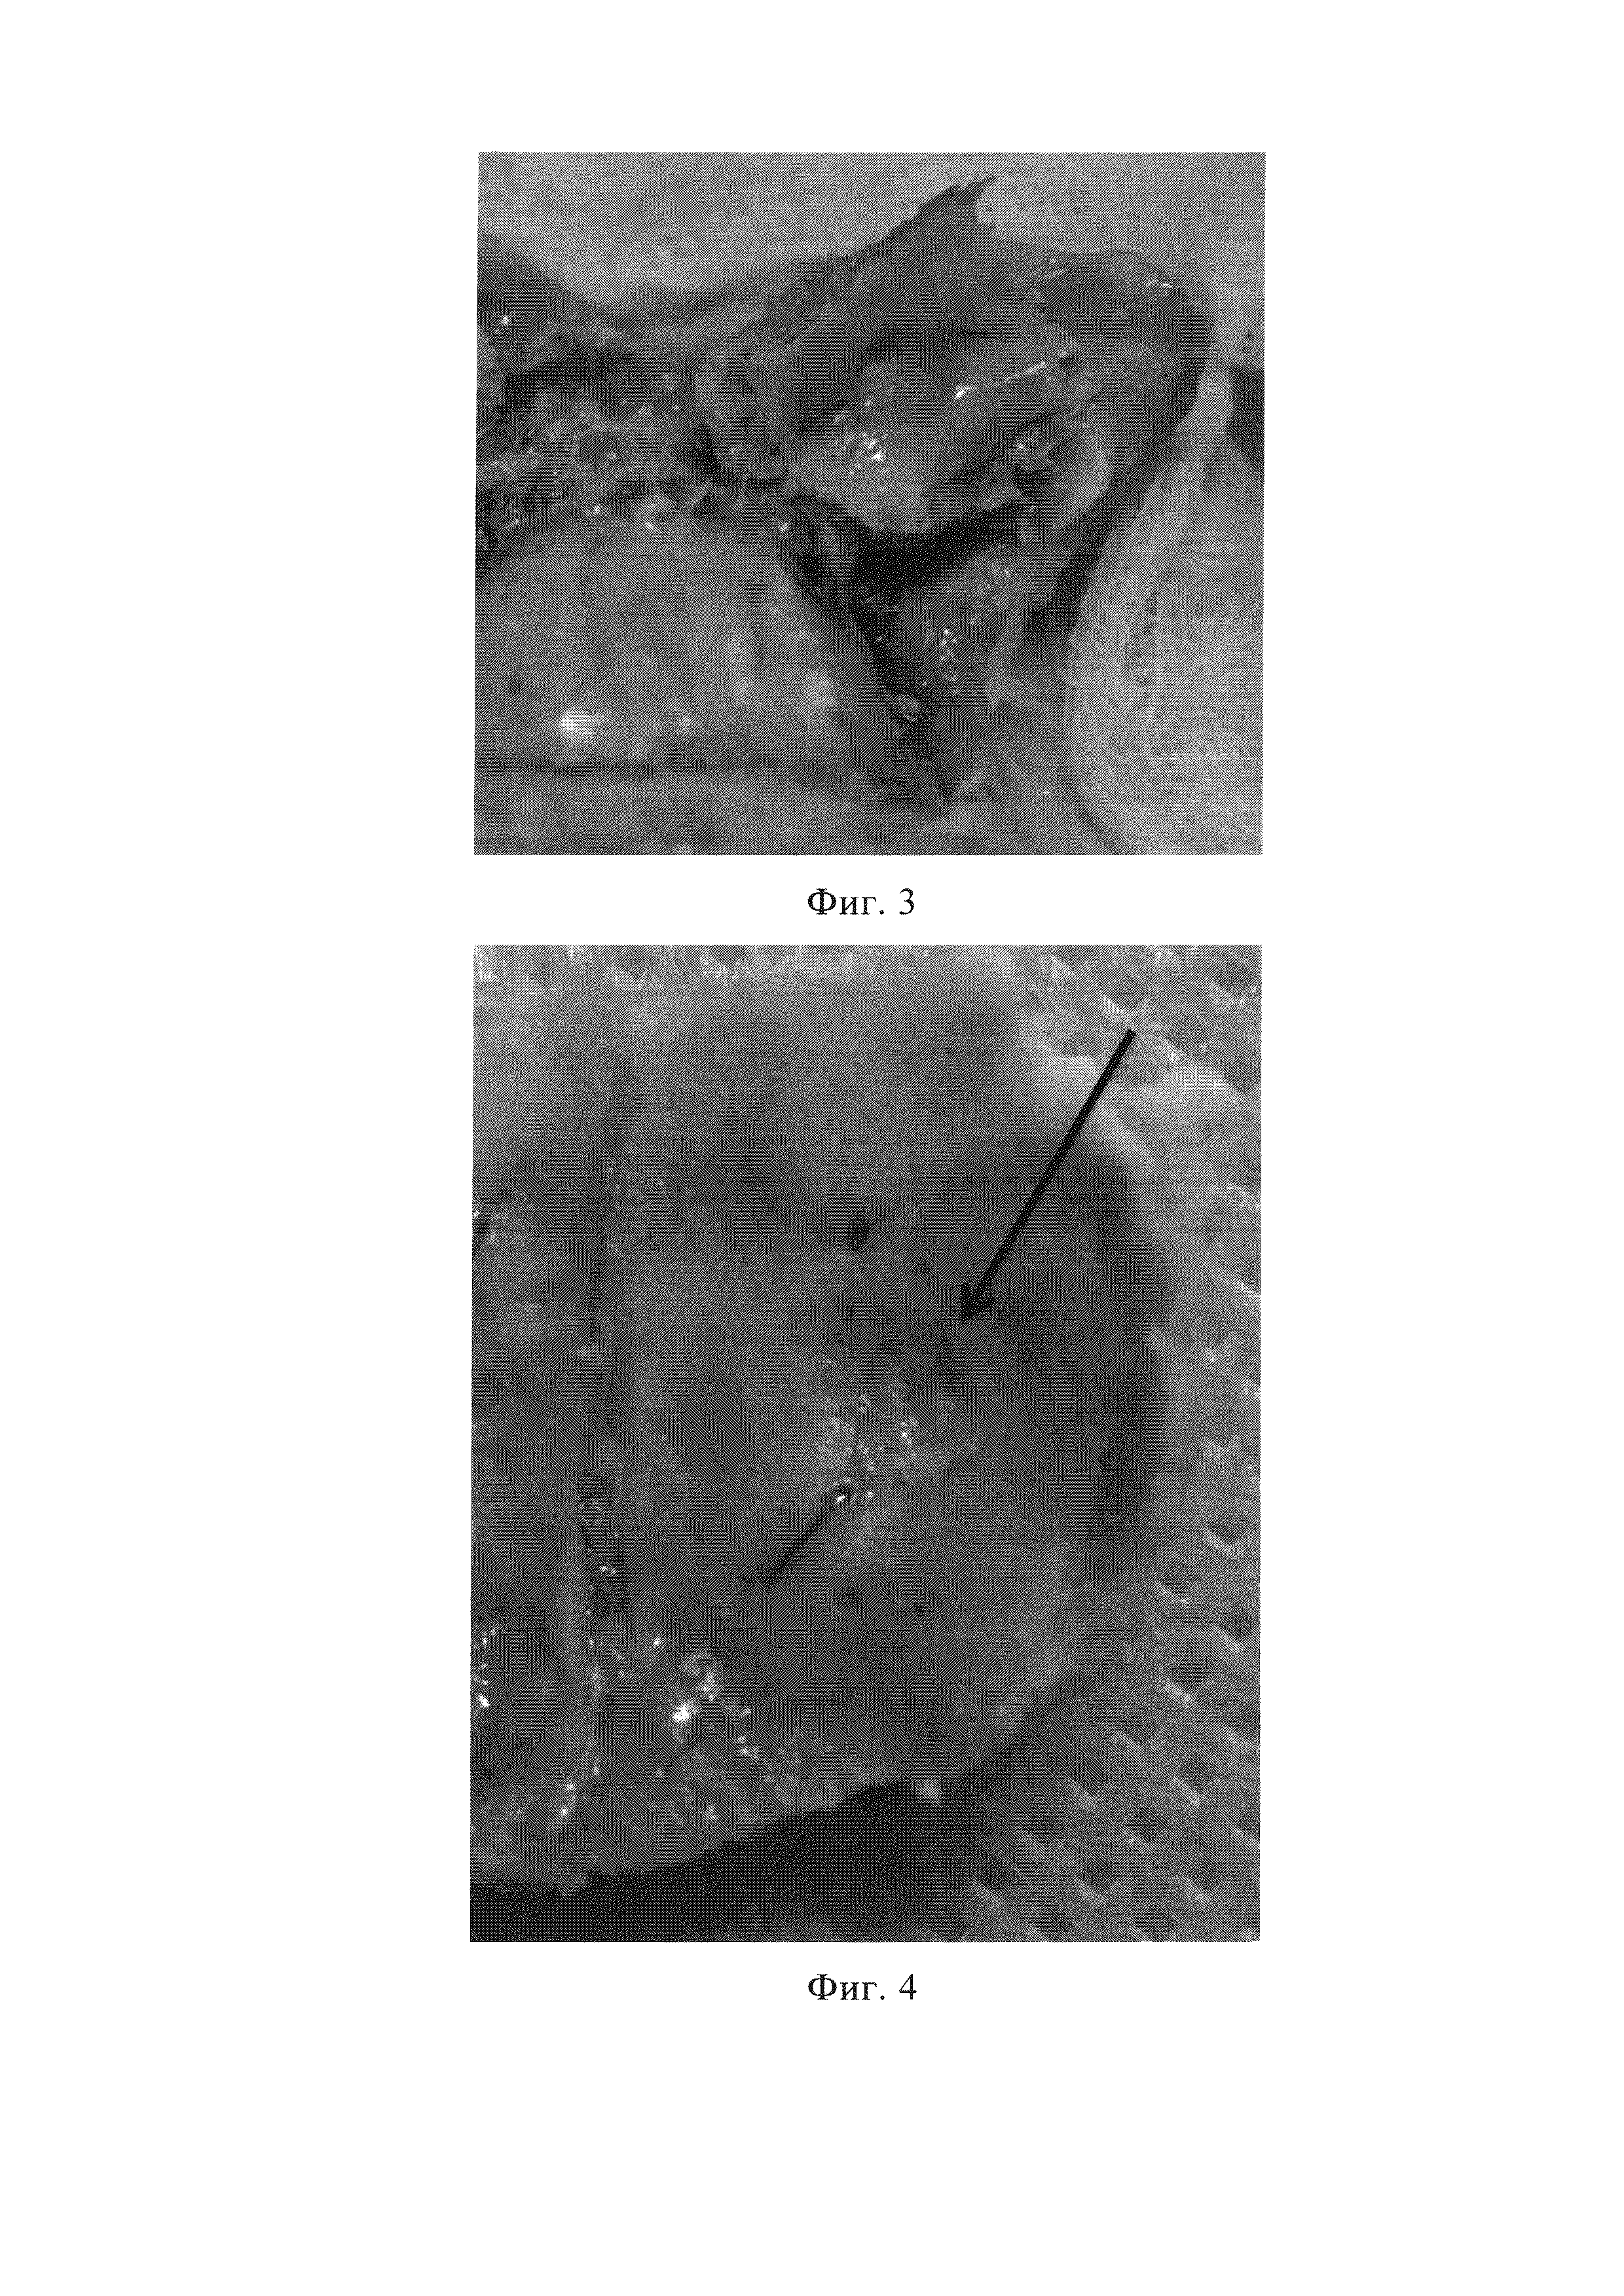

Взятие гистологиии на 24-й день после краниопластики (Фиг. 3).

Виден экспериментальный имплантат из пористого никелида титана, обрастающий костью.

Взятие гистологии на 40-й день после краниопластики (Фиг. 4). Стрелкой указано место экспериментальной трепанации, закрытой пористым имплантатом. Экспериментальный имплант из пористого никелида титана полностью обрастает костью.